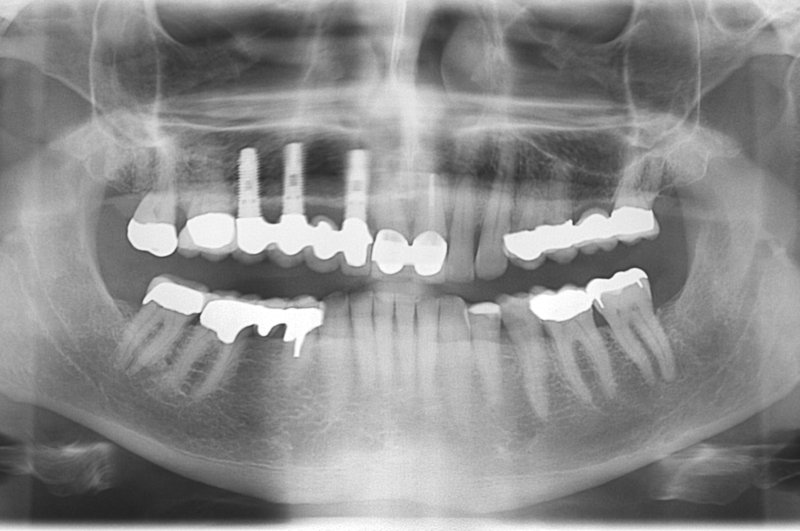

botiss cerabone® & Jason® membrane for GBR - Clinical case by Dr. S. Kovalevsky

Implant insertion in atrophic alveolar ridge